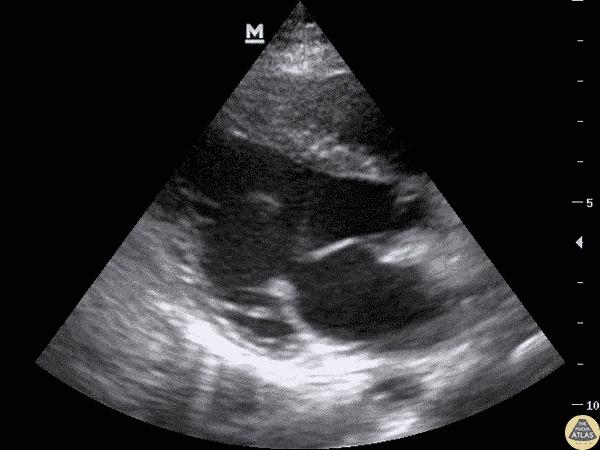

8-year-old with syncope while playing in school. EKG with some non-specific T wave inversions in precodial leads. No murmur, normal heart sounds. POCUS completed for concerning history and EKG changes. Interventricular septal hypertrophy seen on parasternal short and long views (concerning if measurement > 15mm). Dr. Sathya Subramaniam, Pediatric EM Fellow - Kings County/SUNY Downstate